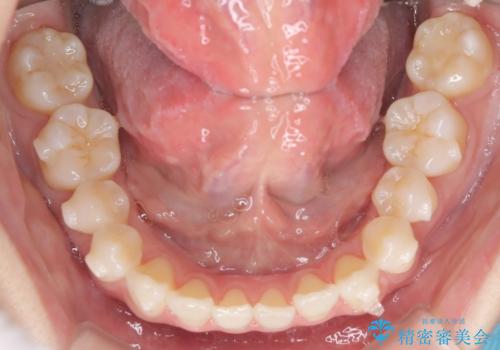

インビザラインモデレートによる前歯の叢生改善|IPR最小限で自然な歯並びへ

- 患者様は、**前歯の叢生(がたつき)**を気にされて来院されました。

できるだけ歯を削らずに、自然な歯並びを手に入れたいというご希望がありました。

診査の結果、中等度の叢生であったため、インビザラインモデレートでの対応が可能と判断しました。

歯へのダメージを抑えるため、IPR(歯間削合)は必要最小限にとどめる方針としました。

前歯の叢生は解消され、自然で調和の取れた歯並びが得られました。

「歯をほとんど削らずにきれいになった」と、患者様にもご満足いただけました。